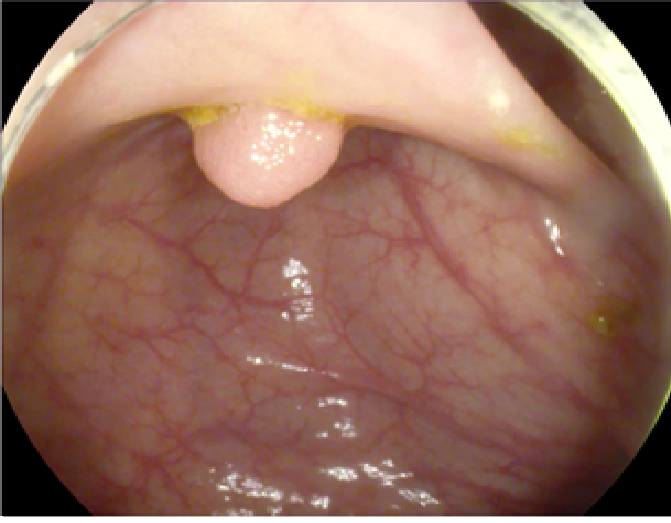

The study used a publicly available dataset of polyp-frames obtained from the ETIS-Larib database [34], containing 196 polyp images. These images were obtained from 34 different colonoscopy videos of 44 different polyps with various appearances and sizes, having a resolution of pixels. The ground truth of polyp areas for polyp datasets is determined by expert video endoscopists. A CNN model trained with such a small amount of data is likely to be meaningless and unstable, so data augmentation was performed on the polyp dataset. Data augmentation had to be performed on the colonoscopy images by considering vivid variations. Otherwise over-fitting would have occurred. In a colonoscopy imagery, polyps exhibits large variations in location, color, and scale. Moreover, variations in brightness and definition also occur due varrying the view-point of the camera. Therefore, in addition to photometric distortions and geometric distortions, we also have considered zooming, shearing, and altering brightness as strategies for data augmentation.

For photometric distortions, we controlled brightness and contrast as an enhancement, while blurring by adding noise with a standard deviation of 1.0. Similarly, for geometric distortions, clock-wise rotation of the polyp images with angles of , , and were performed. Zoom-in and zoom-out with zooming parameters such as 30.00% and 10.00% were performed to obtain different scales of polyp images. Lastly, shearing for both the x-axis and the y-axis was performed to shear the images from left to right and top to bottom, respectively. Fig. 4 shows photometric and geometric forms of image augmentation. In this way, we augmented the data set of the ETIS-Larib database from 196 polyp images to 2,156 images, which is more suitable for training the proposed deep CNN model.

The results shown in Fig. 6 are generated using the proposed deep CNN model on the augmented data set. It can be observed that the proposed model shows better polyp detection performance. As illustrated in Fig. 6, polyps within a frame can be identified at multiple positions, and as noted above in this case, the TP for detection is considered to be 1. The proposed deep CNN model performed better than other benchmark results in terms of the performance metrics listed above, as shown in Table. 2 and Fig. 6.